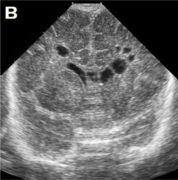

|  | | а - в проекции каудоталамической вырезки определяется кистозного характера включение, размерами 6х5мм, перекрывающее просвет бокового желудочка (перивентрикулярное кровоизлияние в стадии псевдокисты). | б - в проекции каудоталамической вырезки определяется кистозного характера многокамерное включение, размерами 14х6 мм, перекрывающее просвет бокового желудочка (перивентрикулярное кровоизлияние в стадии многокамерной псевдокисты), имеется фрагментация сосудистого сплетения. | |